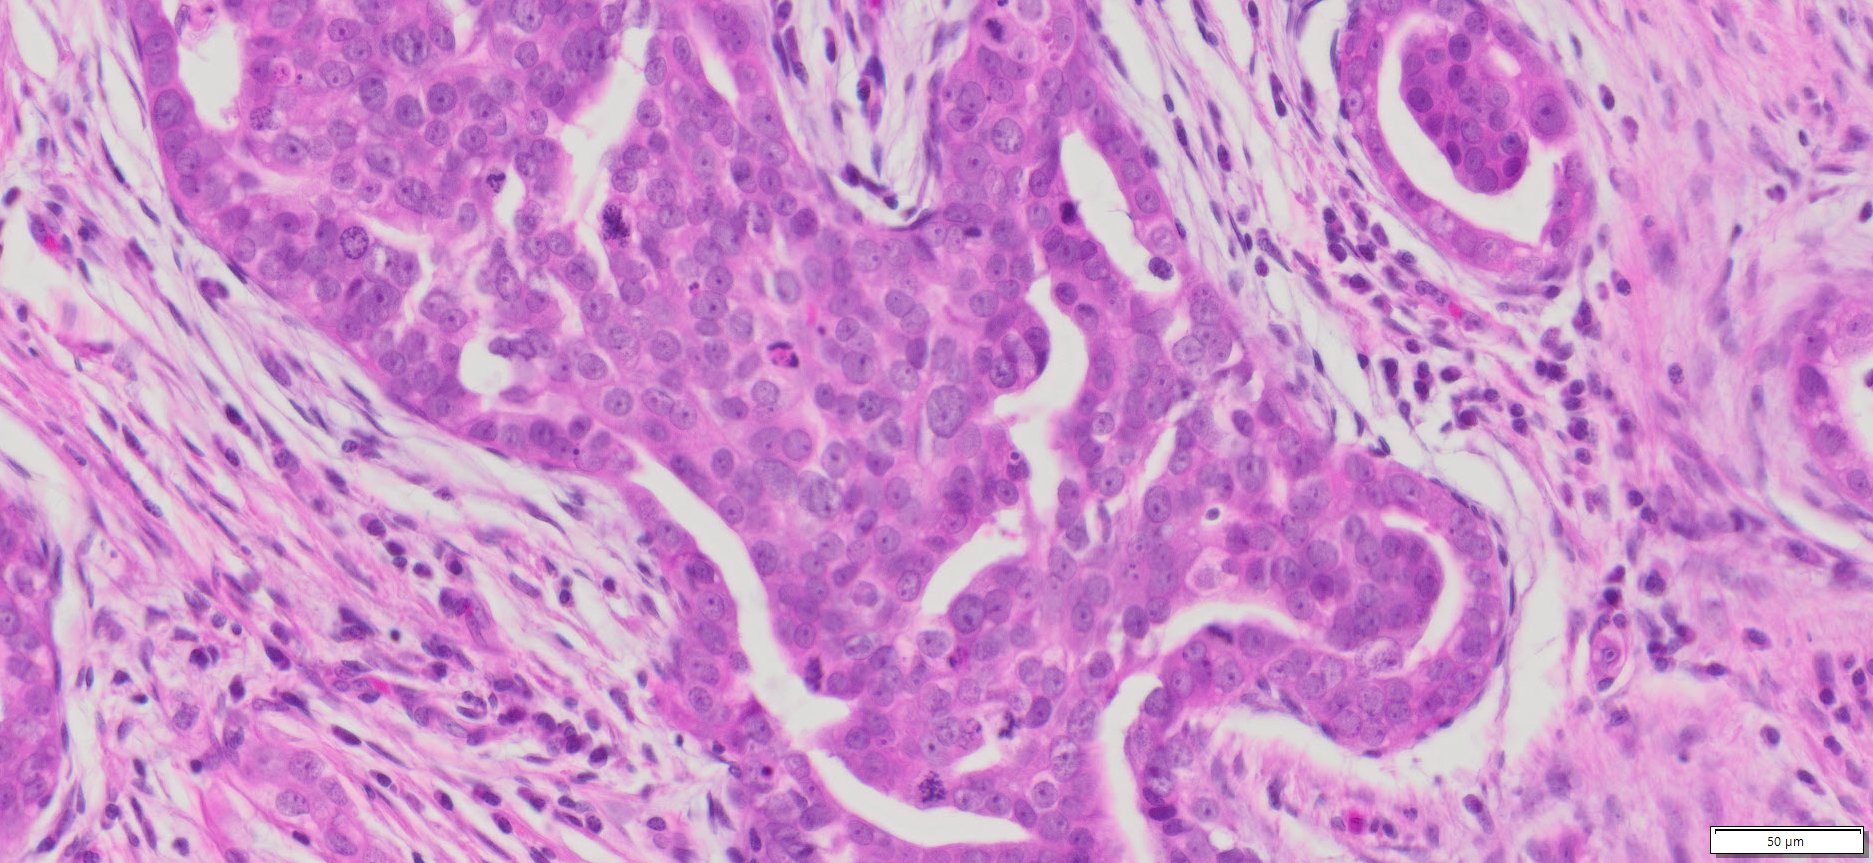

Description

| Tissue | Pathology Diagnosis | Gender/ Age (year) | %Tumor Area | Tumor Grade | TMN/Stage | IHC data |

| Omentum | Human omental high grade serous Carcinoma | Female/67 | 40% | III | NA | MOC-31(+),BER-EP4(+),P53(+), P16(+) |